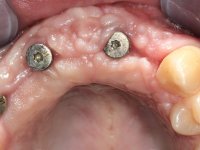

The wax-up allowed us to do a mock-up that worked also as a radiological template. The CT-scan was imported to an implant planning software where three dental implants were simulated, and a surgical guide developed.

10 weeks after the surgery, a first impression was done to do a CAD-CAM provisional bridge (based on the diagnostic wax-up), that worked the soft tissue architecture during two months. This architecture was copied in a second impression by individualizing the impression copings in their emerging profile.

The working model was scanned and the dental technician developed a zirconia framework based on the diagnostic wax-up. This framework try-in was done, the perfect fit was assessed, and a final impression was done with a light silicone.